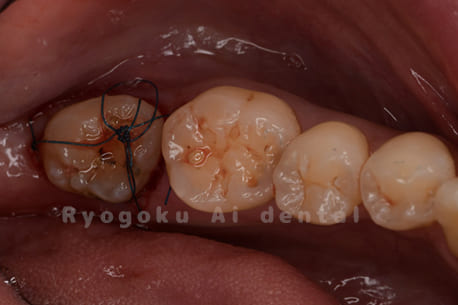

他院で抜歯し、インプラントを進められた患者さんです。親知らずが残っていたため、移植治療がベストと判断し、治療を行いました。

<リスク・副作用>

治療後、痛みや違和感、出血、腫れなどが出る事があります。喫煙者、糖尿病などの方の場合、歯が生着しない場合があります。